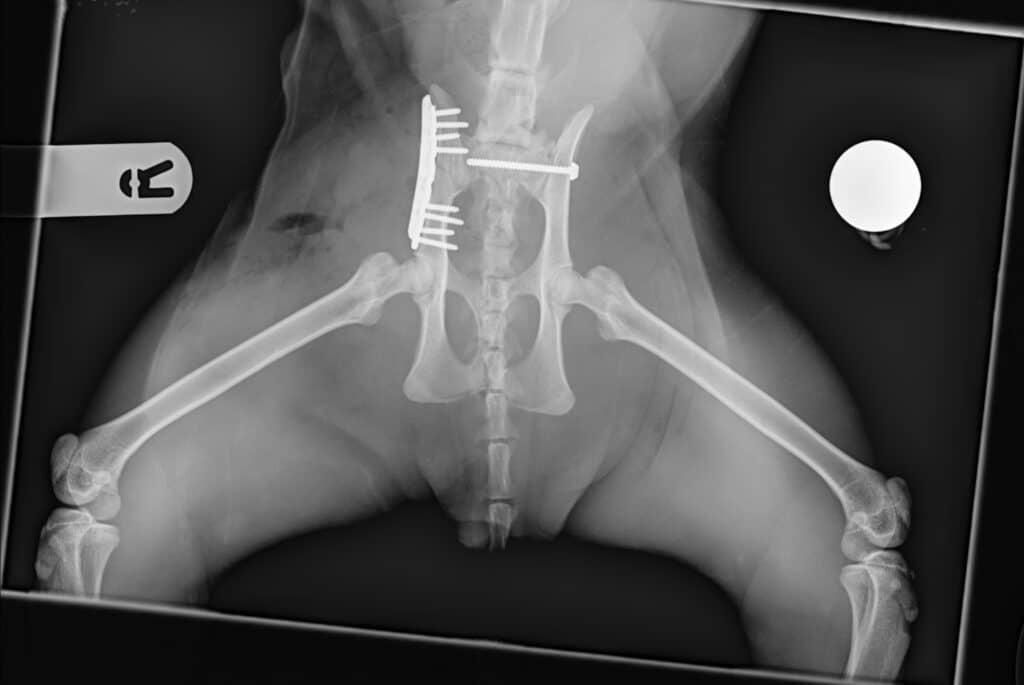

Matthew Eayrs, one of our Consultants in Orthopaedic surgery said: “When Buddy arrived with us, he was in a very serious condition and was not able to walk with a severe right pelvic lameness. A radiograph confirmed severe pelvic fractures which meant Buddy needed an urgent operation to give him the best chance of walking again. The surgery itself involved repairing the fractures with pins. A post-operative radiology revealed good fracture fragment alignment and implant positioning.”

Buddy made good progress after surgery and is able to walk on all of his legs again with no obvious pain.